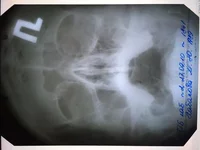

Вот решила к другому сходить врачу(в той же поликлиннике), он сделал снимок,увидел в носу какие то искривления, бугорок, говорит ей гайморит , надо пробивать чистить и т.д.. Вот тут Я совсем не понял, как врачи наши лечат(один одно,другой другое), решил проконсультироваться немного. Что нам делать и как поступить?

снимок прикрепил, скажите по нем видно чтото?

Забыл, есть старое еще фото 2010года( прикрепил)